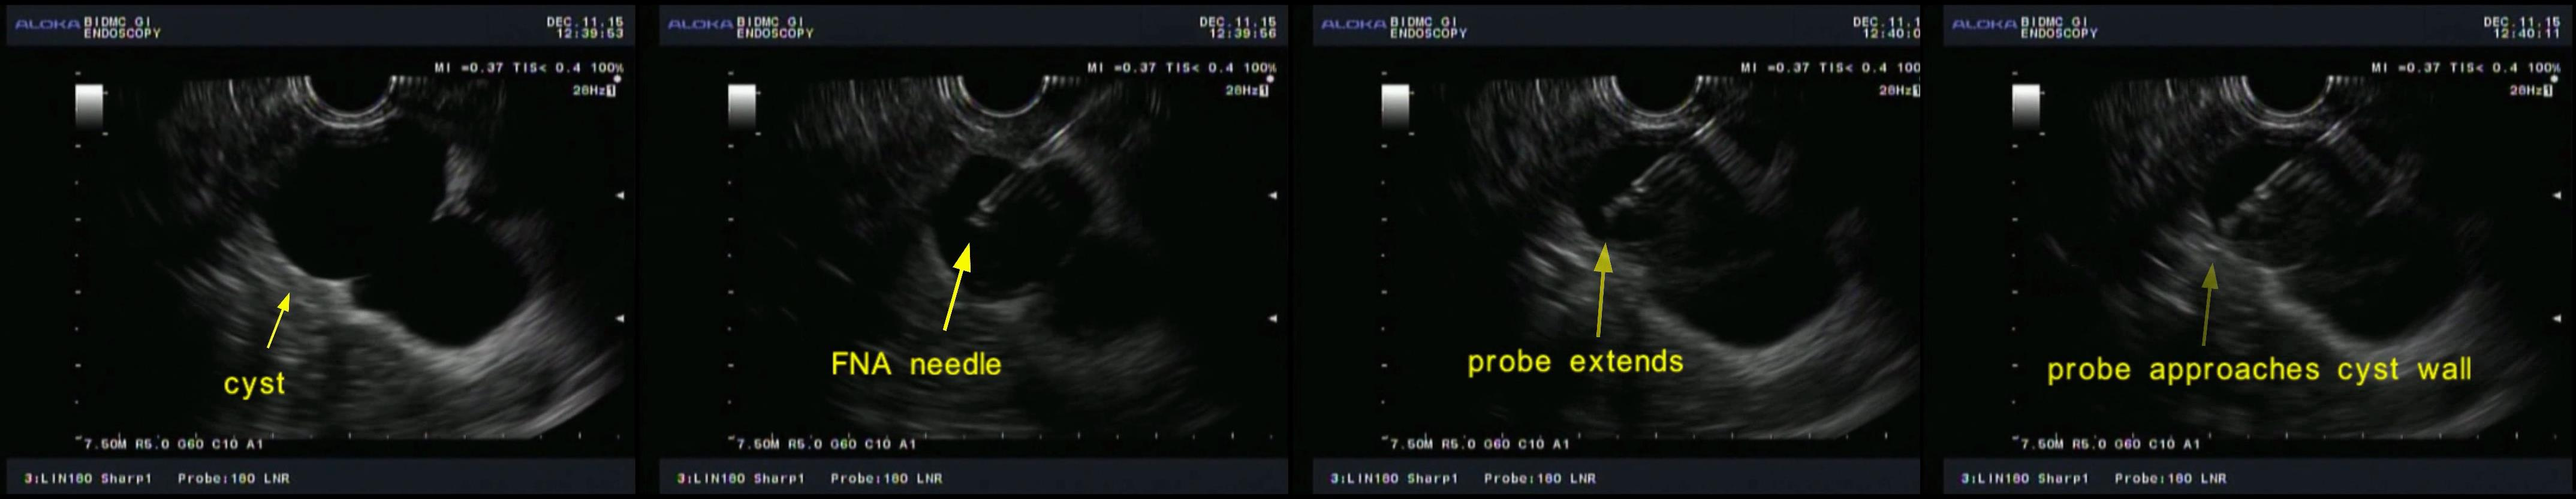

Figure 2. EUS images showing data collection from one of multiple spatial locations in a pancreatic cyst.

Encouraged by our quite successful application of light scattering spectroscopy in the esophagus, we decided to try it for diagnosing malignancy in pancreatic cysts. The most challenging part was to develop a tiny fiber optic probe, compatible with the miniature, half millimeter in diameter, EUS-FNA needle, capable of enhancing the contribution of the light scattering signal coming from the epithelial cells. Our interdisciplinary team solved this problem by constructing a spatial gating light scattering spectroscopy (LSS) probe, which uses the fact that the backscatter signal coming from epithelial cells decreases with the distance between the source and detector fibers significantly faster than the multiple scattering signal (Fig. 1). With this probe our new LSS fine needle aspiration compatible instrument provides highly accurate in vivo identification of the malignant potential of pancreatic cysts during endoscopy (Fig 2. and Fig. 3).